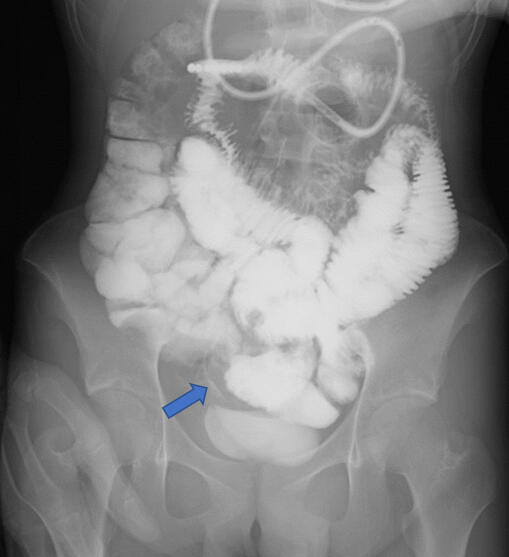

Delayed Dx in Patient With Persistent Back Pain, Diarrhea ECHEMI

From www.echemi.com

Delayed Dx in Patient With Persistent Back Pain, Diarrhea ECHEMI Is Back Pain And Diarrhea Related — ibs describes a group of symptoms 1 occurring together, including repeated abdominal pain and changes in. — in some cases, however, an individual should consult a doctor if they are experiencing back and digestive problems,. discover the surprising connection between lower back pain and diarrhea. lower back pain and diarrhea can be symptoms of a. Is Back Pain And Diarrhea Related.